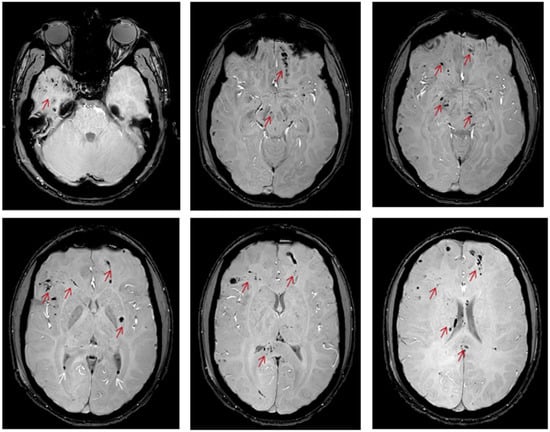

MRI is a far more sensitive imaging modality than CT scan for detecting small white matter lesions, but it is infrequently available in the acute phase [3,16,17,18]. Despite the progress that has been achieved in detecting TAI lesions, the only definitive way to confirm the diagnosis is via brain biopsy or post-mortem histopathological evaluation [4]. Figure 1 presents the appearance of TAI lesions in different imaging modalities of one patient with TAI (Figure 1).

An unenhanced CT scan is the imaging modality of choice for the initial evaluation of patients with TBI [4]. In the acute phase, the primary aim of the CT scan is to detect the presence of hemorrhagic lesions or contusions and evaluate the risk of brain herniation. CT scan findings and clinical presentation will determine the need for acute neurosurgical intervention [4,14,15,19,20,21,22]. Because patients with TAI usually present with LOC and low GCS on admission, they almost always undergo an unenhanced CT scan [4]. Due to local capillary damage, axonal lesions are usually not detectable on CT scans if they are not accompanied by significant hemorrhagic elements, usually seen as hyperdense small petechiae. Hence, the hallmark of TAI on CT scans is the presence of diffuse bihemispheric petechiae lesions in the gray–white matter interface (Figure 1a). The CT will detect approximately 20% of these lesions as small hypointense (under 1–2 cm) areas. Since TAI lesions are usually underseen on CT, it has been suggested that their presence is related to extensive brain damage and poor outcome, but this has been recently questioned [14,19]. Despite the disadvantage of CT for being insensitive in detecting TAI lesions, these findings can be indirectly used to diagnose TAI. In a recent systematic review of the literature, Figueira et al. found that TAI lesions are usually accompanied by intraventricular or subarachnoid hemorrhage. Specifically, the presence and the extent of intraventricular or subarachnoid hemorrhage positively correlate with the existence and severity of TAI. At the same time, the absence of these hemorrhagic lesions rules out significant axonal injury [19].

Conventional MRI is approximately two to three times more sensitive than CT in detecting TAI lesions [13]. However, the sensitivity is lower for the detection of non-hemorrhagic lesions. The signal is usually hyperintense in T2 and FLAIR sequences, while the signal varies in T1 sequences; it is low when the lesion is non-hemorrhagic or high when the lesion has hemorrhagic components (Figure 1b–d) [13,23]. The histopathological grading proposed by Adams et al. [23] has also been utilized in the imaging classification of these lesions. In 2017, Hamdeh et al. [13] proposed an extended classification of the typical three-grade system based on the observation that TAI lesions in the substantia nigra and the tegmentum were independent risk factors for poor outcome and hence represented a distinct fourth grade. Except for the conventional MRI sequences, other MRI sequences such as susceptibility-weighted imaging (SWI), diffusion-weighted imaging (DWI), and diffusion tensor imaging (DTI) have substantially improved the diagnostic sensitivity of MRI to detect TAI lesions [24].

When TAI lesions have hemorrhagic components, techniques that detect blood breakdown products, such as the conventional gradient recalled echo (GRE)-T2* and the advanced SWI (Figure 1e and Figure 2), are preferred. The SWI enhances the contrast of GRE-T2* sequences by combining T2*-magnitude and phase images [25]. Hence, the SWI can detect smaller lesions. In a study of seven young patients with TAI, Tong et al. found that SWI could detect ten times more hemorrhagic lesions than GRE-T2* (1038 vs. 162) [25]. In a larger study including 40 young patients, it was found that the number and volume of hemorrhagic lesions depicted in SWI significantly correlated with patients’ functional outcomes [26]. However, these techniques can only distinguish TAI lesions in the sub-acute or chronic phase [25] because they detect blood breakdown products and hence can mainly support the diagnosis of TAI in cases of diagnostic doubt.

In highly organized structures that contain macromolecules such as proteins or membranes, free diffusion of the water molecules is restricted [18]. Diffusion MRI creates contrast MRI images by detecting the degree of random motion of water molecules [18,27,28]. It is a very sensitive technique in detecting brain lesions within the first 3 h after the incident, contrary to the conventional CT and MRI techniques which require at least 8–12 h to visualize the infarct [29]. Ischemia generates cellular cytotoxic edema, contrasting with the surrounding non-ischemic tissues. Similarly, after TAI, the shearing forces cause local edema and disruption of the axonal architecture, thus resulting in alterations in diffusion images (Figure 1f,g).

Figure 1. 17-Year-old male with traumatic axonal injury (unpublished data) (a) CT scan on admission shows hyperdense foci (microhaemorrhage) in the gray–white matter junction of the left frontal lobe (red arrow) and hypodensity of the splenium of the corpus callosum (yellow arrow). (b) MRI, three days later, axial T1WI shows a hyperintense lesion at the gray–white matter junction of the left frontal lobe compatible with subacute hemorrhage (red arrow) and hypointense lesions in the deep white matter of the right frontal lobe and the slpenium (yellow arrow). (c) MRI axial T2WI, and (d) FLAIR images show the left frontal lobe lesion with low signal (red arrow) and the lesions of the deep white matter of the right frontal lobe and the splenium with high signal intensity (yellow arrow). (e) MRI axial SWI sequence shows multiple low signal intensity lesions compatible with haemorrhage mainly located in the gray–white matter junction of fronto-occipital lobes and the right side of the splenium of corpus callosum (red arrow). (f) DWI image (g) and ADC parametric map reveal restricted diffusion within the splenium of the corpus callosum (red arrows), compatible with cytotoxic oedema. Key: CT, computed tomography; MRI, magnetic resonance imaging; WI, weighted imaging; SWI, susceptibility-weighted imaging; DWI, diffusion-weighted imaging.